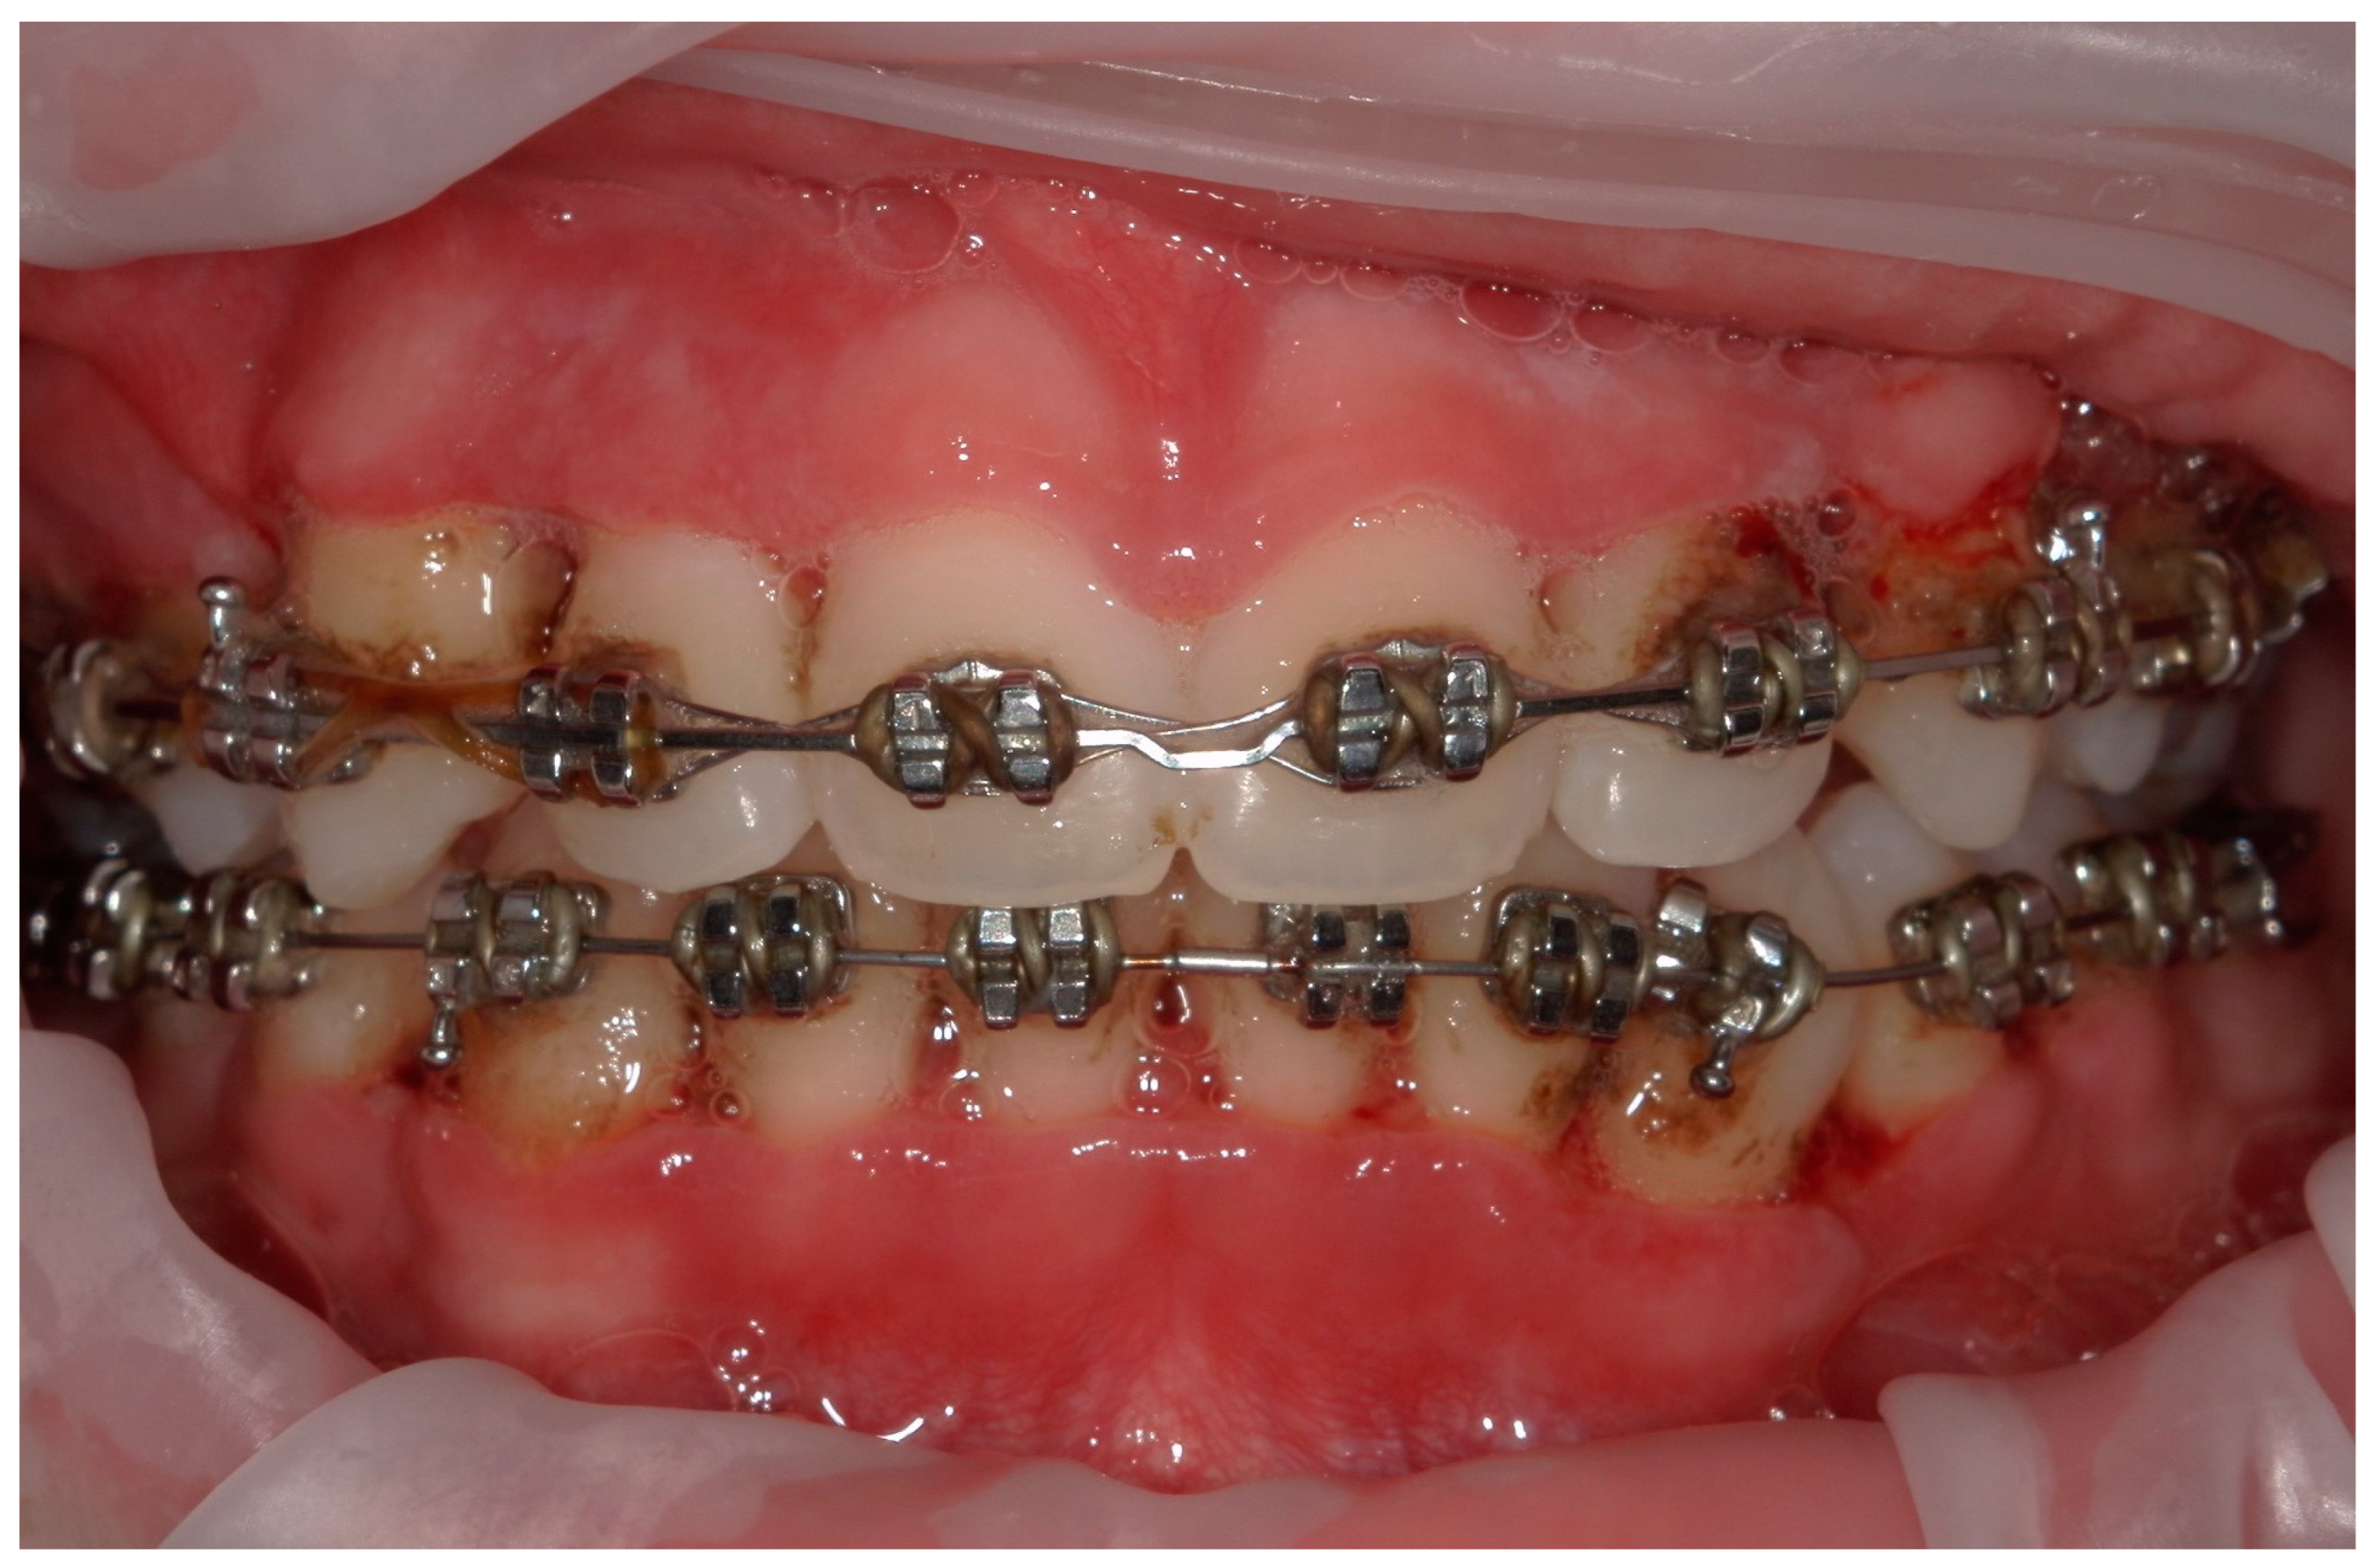

4.2. Case 2